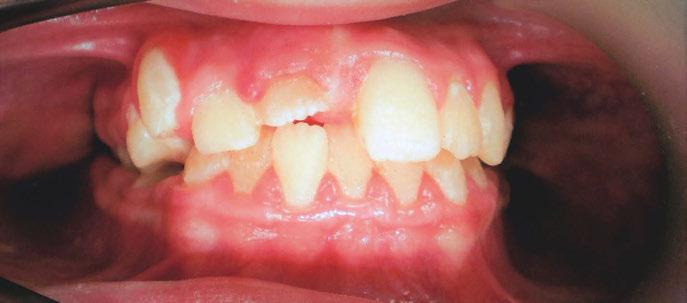

The history of myofunctional therapy in conjunction with orthodontic treatment dates to as early as 1906 with the publication of American orthodontist Alfred Rodgers’ “Living Orthodontic Appliance.” Rodgers presumed that muscle alone would correct a malocclusion.1 To further this claim, Edward Angle theorized that “every malocclusion has a myofunctional cause.”2 Angle’s contribution to myofunctional therapy relied primarily on fixed orthodontic appliances (Figure 1). However, the myofunctional component of orthodontics with fixed appliances fell out of favor when relapse occurred in a high percentage of patients coupled with time-consuming techniques to achieve results. Hence, tooth-centered orthodontics with extractions or self-ligating brackets without the need for extractions grew in popularity (Figure 2). Nevertheless, post-orthodontic relapse was still problematic, requiring permanent retainers. As George Hahn once wrote in his publication “Retention — The Stepchild of Orthodontia,” Irrespective of the length of time a tooth is held in its new position … upon release, it will seek a place where it is in balance.”3 Myofunctional therapy has made significant strides in using specifically designed exercises to bring oral, facial, and